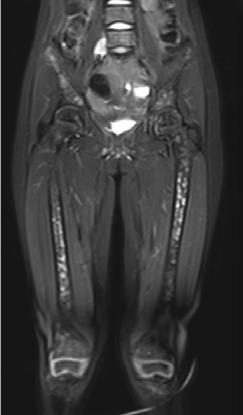

El neuroblastoma es la neoplasia sólida extracraneal más frecuente en niños. Al momento del diagnóstico, el 50% de los pacientes presentan enfermedad metastásica. Estos pacientes tienen un alto riesgo de enfermedad refractaria o recurrente y un pronóstico adverso. Durante las últimas décadas, la medicina nuclear ha sido fundamental para la estadificación y la evaluación de la respuesta al tratamiento del neuroblastoma. Actualmente, la técnica de imagen nuclear estándar es la gammagrafía corporal total con meta-[ 131I ]yodobencilguanidina ([ 131I ]mIBG) en México, generalmente combinada con tomografía computarizada por emisión monofotónica con tomografía computarizada (SPECT-CT). Sin embargo, el 10% de los neuroblastomas no son ávidos por este radiofármaco y las imágenes con [131I]mIBG tienen una resolución espacial relativamente baja, lo que resulta en una sensibilidad limitada para lesiones más pequeñas, además de conferir mayor dosis de radiación al paciente. Se necesitan métodos más precisos para evaluar la extensión total del neuroblastoma debido a su comportamiento y variabilidad tumoral heterogénea con el fin de optimizar las estrategias de tratamiento. La imagen híbrida ha llevado a la introducción de radiotrazadores compatibles con la tomografía por emisión de positrones (PET) en neuroblastomas, como [ 124 I]mIBG, [18F]mFBG, [18 F]FDG, [ 18F]Octreotide, 6[18F]F-DOPA y [11 C]mHED. La metodología PET ofrece mayores y múltiples ventajas sobre la SPECT, incluida una resolución superior y un rango tomográfico de cuerpo entero, además del beneficio de la información en las diversas secuencias al combinarlo con la resonancia magnética.

Femenino de 7 años con diagnóstico de Neuroblastoma, se realiza PET/RM con [18F]F-DOPA para estadiaje, con evidencia de lesión primaria a nivel de retroperitoneo y conglomerados locoregionales así como infiltración a médula ósea del esqueleto axial y apendicular (Figura 1A), posteriormente la paciente fue tratada quirúrgicamente con resección de la lesión primaria así como tratamiento con inmunoterapia y transplante autólogo de médula ósea además de radioterapia. Al presentar refractariedad al tratamiento comentado, se plantea la posibilidad de administrar Lutecio (177Lu) oxodotreotide, por lo que se sugiere realizar PET/RM con [18F]Octreotide para valorar expresión de receptores de somatostatina y considerar la terapia con radionúclidos para receptores de péptidos (PRRT), el estudio muestra evidencia de sobreexpresión anormal de dichos receptores en retroperitoneo, espacio subpleural izquierdo además de esqueleto axial y apendicular (Figura 1B).

Estudio PET con 6-[18F]DOPA 3A) y [18F]OCTREOTIDE 3B) en cortes coronales de secuencias T2 de miembros pélvicos y con imágenes fusionadas, donde se identifica mayor sobreexpresión anormal de los receptores de somatostatina al compararlos con 6-[18F]DOPA, y que hace candidata a la paciente para PRRT.